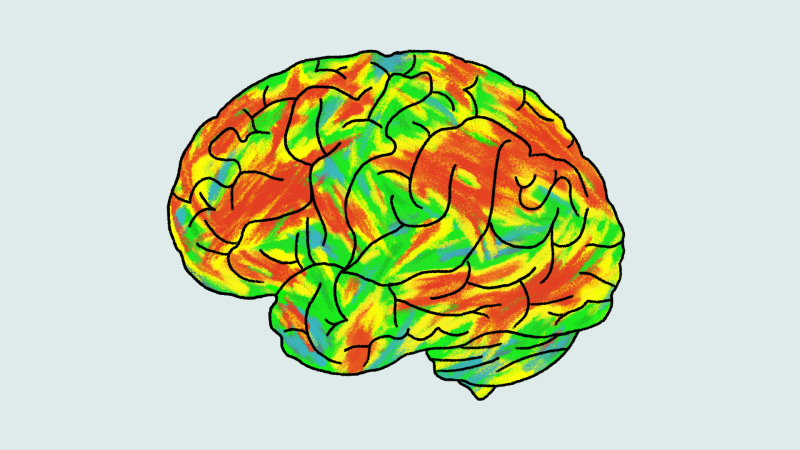

Psilocybin works on a different part of the brain than antidepressants, expert says. The psychedelic zeros in on the brain’s ruminative area, where thoughts run in a circular wheel of negativity many find hard to stop. Brain scans taken before, during and after people are tripping on psilocybin show the brain becomes desynchronized —disrupting those negative thoughts and allowing people to see themselves differently.

At six weeks, the study found no significant difference in depression scores between the antidepressant and psilocybin groups. Brain scans, however, showed a different story.

“The brains of people on psilocybin had increased flexibility, a greater ability to switch between different brain states,” said Nutt, who was a coauthor on the study.

Regardless, the study found people who responded best to psilocybin on brain scans at six weeks reported the lowest levels of depression at six months, Nutt said.

“The more flexible a patient’s brain was three weeks after one trip, the better their outcome on depression at six months,” Nutt said. “There’s a biological, physiological change in the brain as a result of psilocybin — which you can see at three weeks after a trip — that predicts clinical outcome.